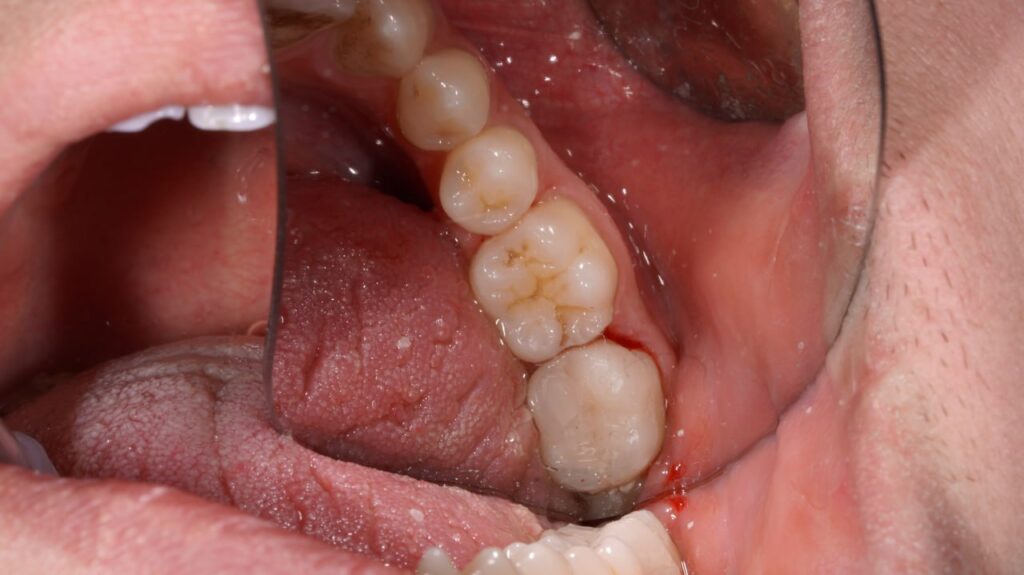

آنلی یک ترمیم سفارشی است که برای دندان‌های پشتی (آسیا) کاربرد دارد. زمانی از آنلی استفاده می‌کنیم که پوسیدگی یا آسیب، بخشی از تاج دندان را درگیر کرده باشد، اما سطوح جونده و یک یا چند تیغه جانبی دندان هنوز سالم باشند.

مشخصه کلیدی: آنلی درون حفره دندان قرار می‌گیرد و به سطوح داخلی (حفره) می‌چسبد. آنلی به اندازه‌ای وسیع نیست که روی تیغه‌های دندان را بپوشاند.

روکش نیز یک ترمیم سفارشی برای دندان‌های پشتی است، اما وسعت بیشتری نسبت به آنلی دارد. زمانی از روکش استفاده می‌کنیم که آسیب، یک یا چند تیغه (دیواره) جانبی دندان یا سطح جونده وسیع‌تری را درگیر کرده باشد، اما هنوز نیاز به روکش کامل نباشد.

مشخصه کلیدی: روکش بخشی از سطح جونده دندان و یک یا چند تیغه جانبی را می‌پوشاند. این روش مانند یک کلاهک جزئی عمل می‌کند.

به زبان ساده: آنلی “درون” دندان می‌رود، در حالی که روکش “روی” بخشی از دندان را می‌پوشاند. روکش نسبت به آنلی، پوشش و حمایت بیشتری از ساختار دندان به عمل می‌آورد.